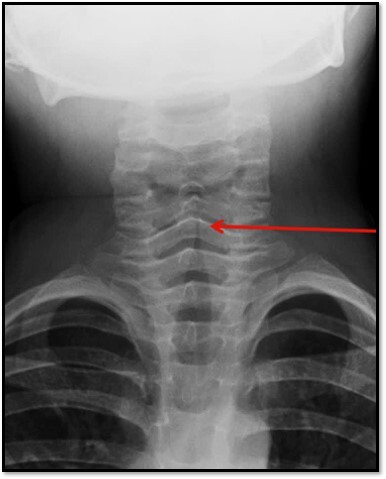

27

What pathology is seen here?

Eppiglottitis (see the red arrow pointing to thumb print sign)

26

What is the radiographic sign of Epiglottitis?

Thickened epiglottis (Thumb sign) on a lateral soft tissue neck